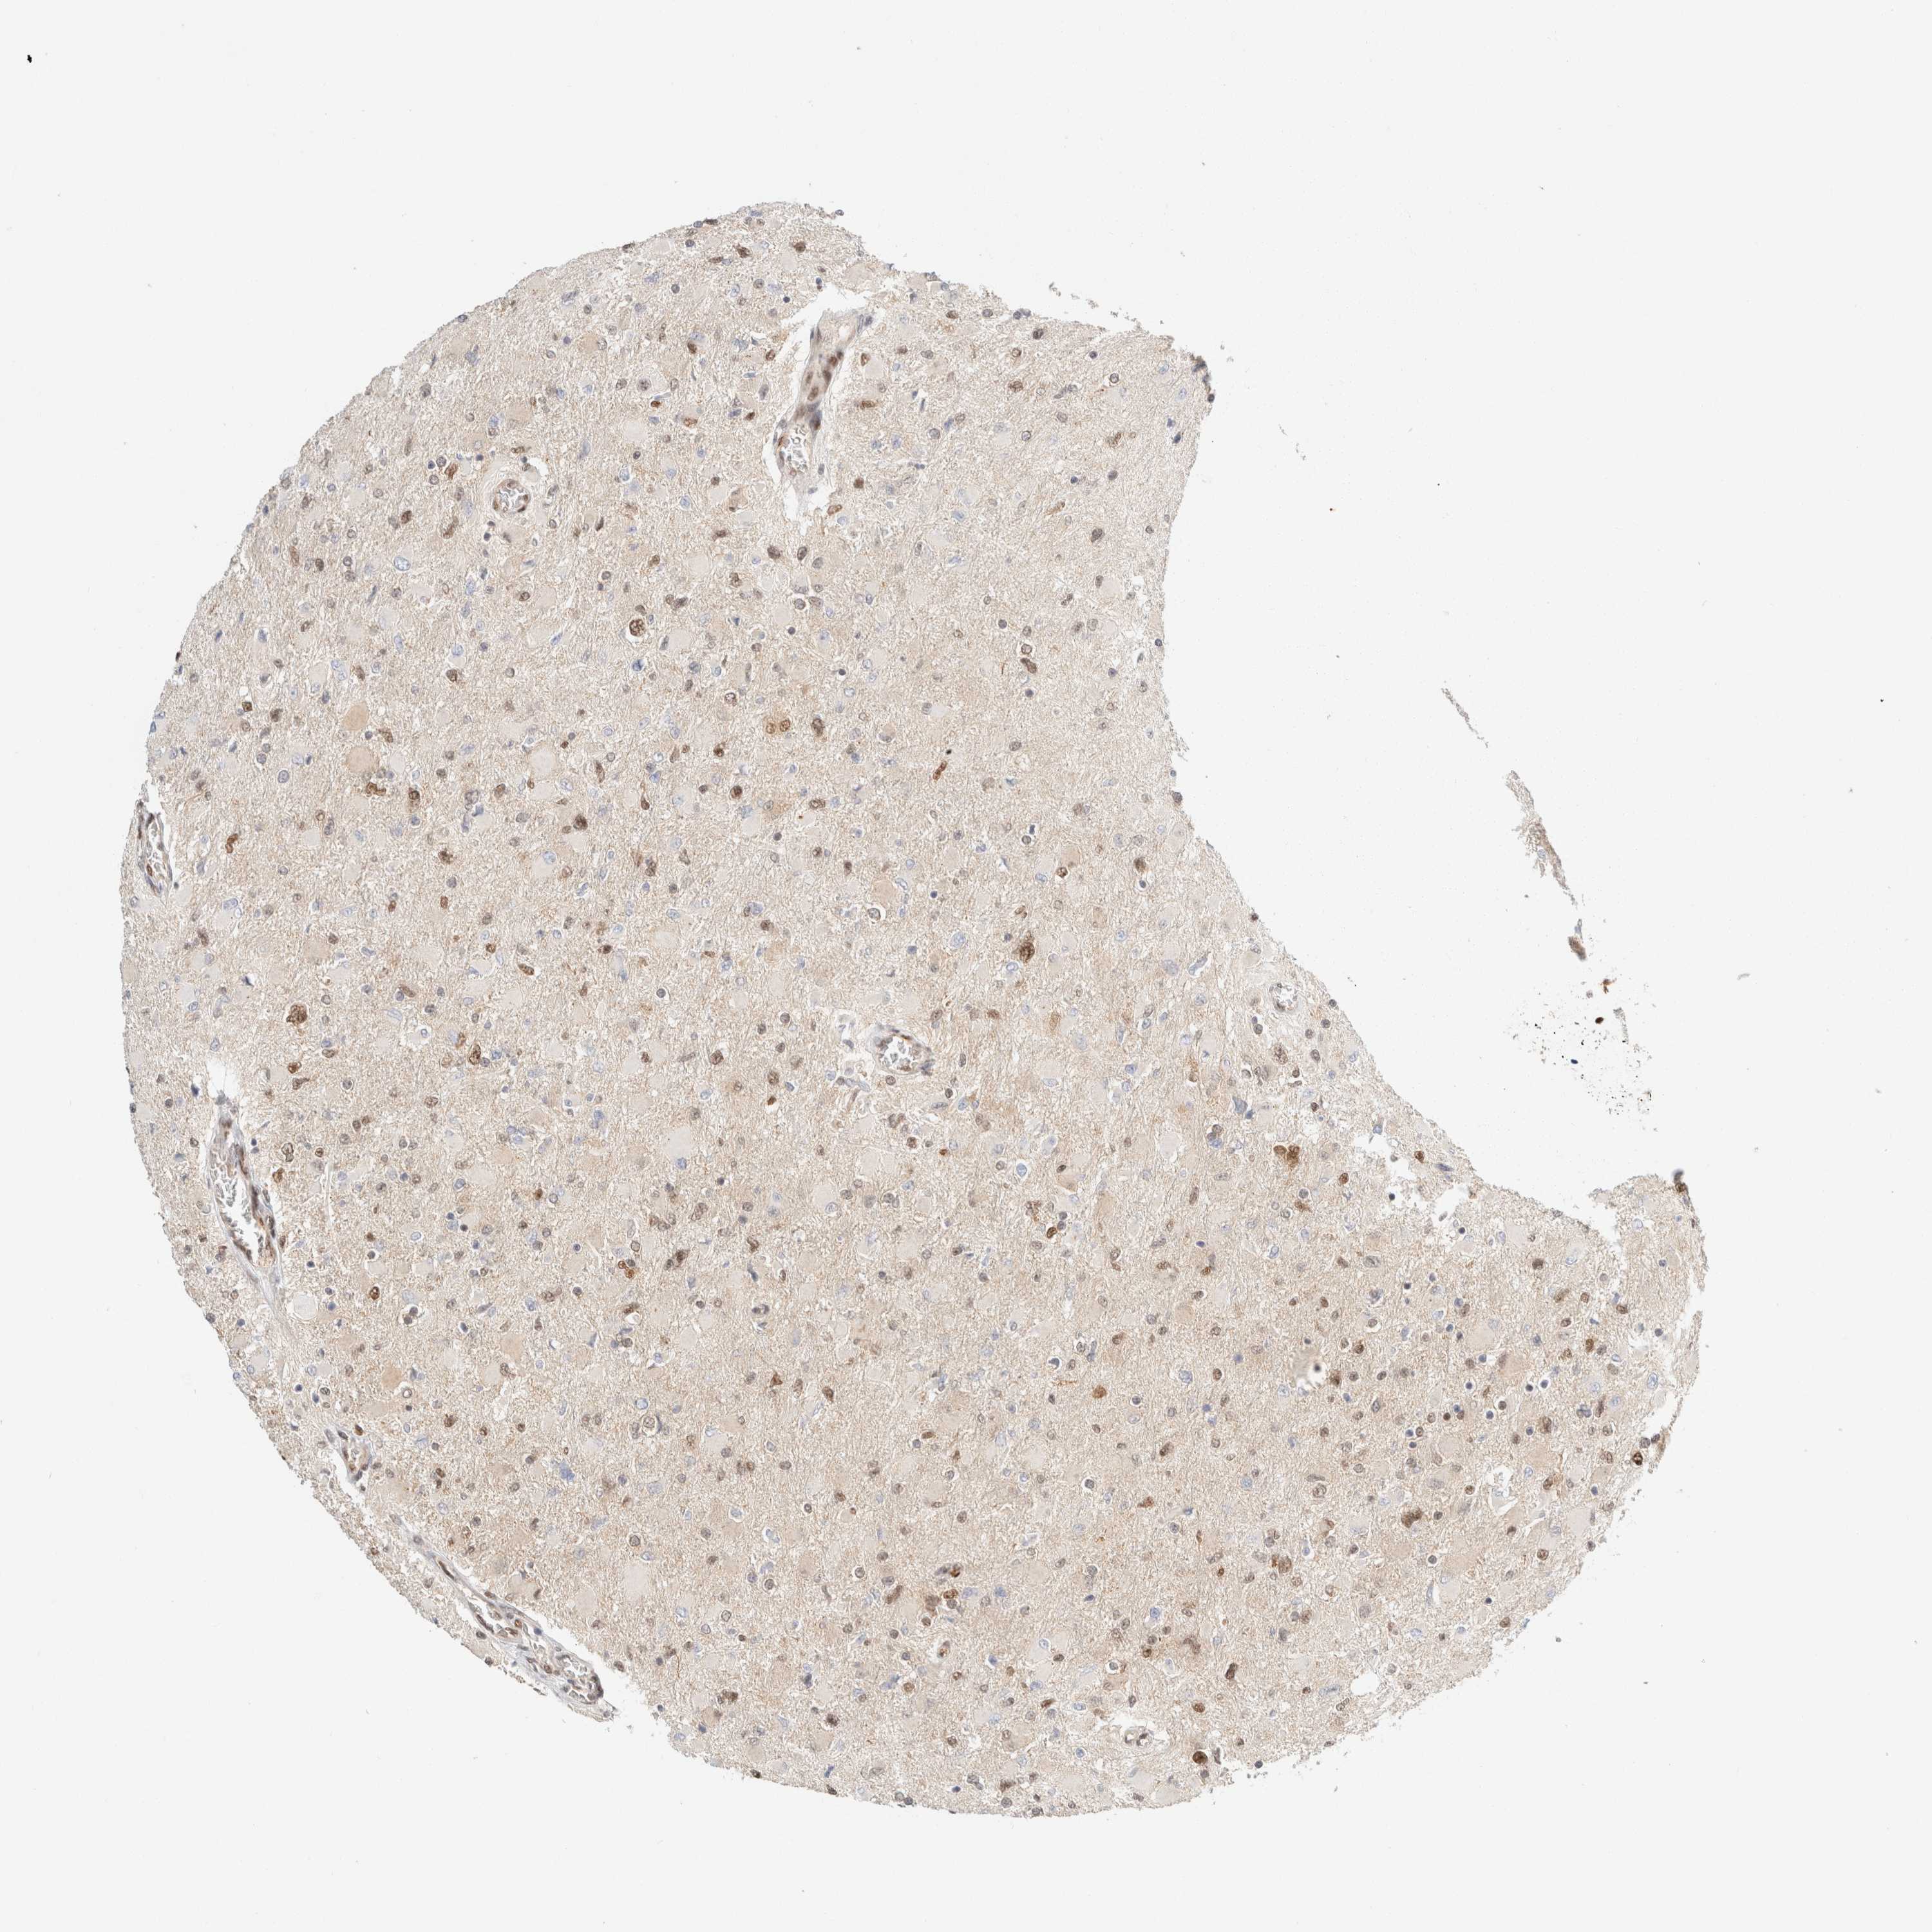

GLIOMA - Protein expressioni

A mouse-over function shows sample information and annotation data. Click on an image to view it in a full screen mode. Samples can be filtered based on level of antibody staining by selecting one or several of the following categories: high, medium, low and not detected. The assay and annotation is described here.

Note that samples used for immunohistochemistry by the Human Protein Atlas do not correspond to samples in the TCGA dataset.

Antibody stainingi

Antibody staining in the annotated cell types in the current human tissue is reported as not detected, low, medium, or high, based on conventional immunohistochemistry profiling in selected tissues. This score is based on the combination of the staining intensity and fraction of stained cells.

Each image is clickable and will lead to virtual microscopy that enables deeper exploration of all samples and also displays staining intensity scores, fraction scores and subcellular localization as well as patient and tissue information for each sample.

Antibody HPA024630

Staining

High

Medium

Low

Not detected

Intensity

Strong

Moderate

Weak

Negative

Quantity

>75%

75%-25%

<25%

None

Location

Nuclear

Cytoplasmic/membranous

Cytoplasmic/membranous,nuclear

Glioma, malignant, High grade

Glioma, malignant, Low grade